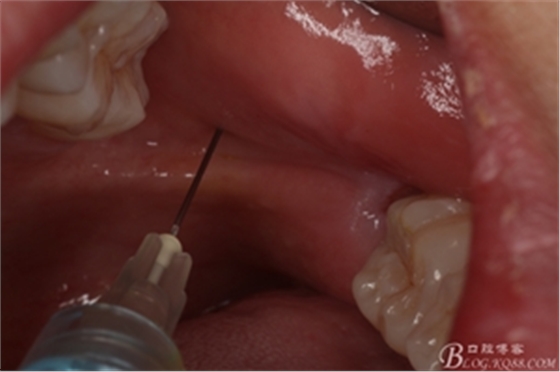

圖5.術(shù)前做好全面的檢查和風(fēng)險(xiǎn)評(píng)估,開(kāi)始局部無(wú)痛麻醉。